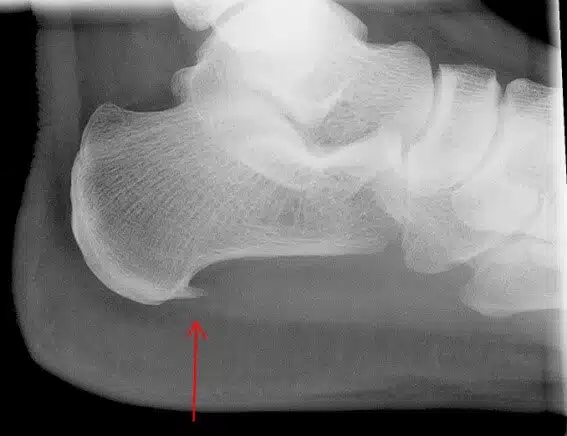

الشوكة العظمية هي عبارة عن نتوء عظمي يتكون في كعب القدم بسبب ترسبات الكالسيوم في منطقة الكعب وينتج عنها شعور مؤلم للكثير من الأشخاص ويكون الألم في أسفل القدم وحول الكعب وهذا الألم يكون نتيجة لالتهاب الأنسجة التي تعمل على ربط أصابع القدم بالكعب.

• الفحص بالأشعة: يعتبر من أدق الفحوصات التي قد يحتاج المريض الخضوع لها وذلك لأنها تكشف عن شكل العظام من الداخل وتحديد مستوى ودرجة الإصابة التي يعاني منها المريض والتأكد من عدم وجود أي جزء أخر متضرر، ومن أهم هذه الأشعة التصوير بالرنين المغناطيسي والأشعة السينية.